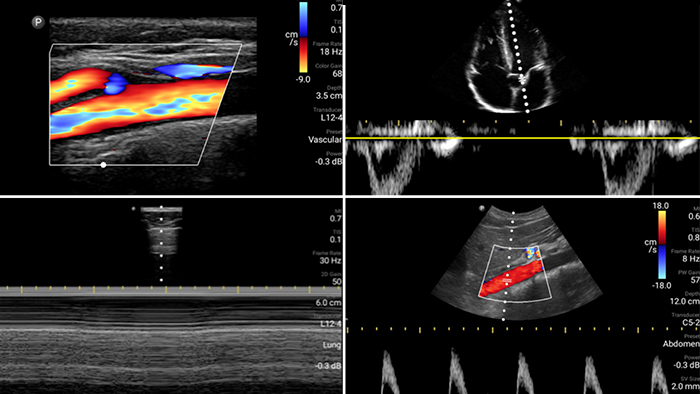

Kontinuierliche Unterstützung durch Lumify

Beurteilen, diagnostizieren und behandeln Sie Ihre Patienten in Minuten mit einer Multi-Point-POCUS-Untersuchung.